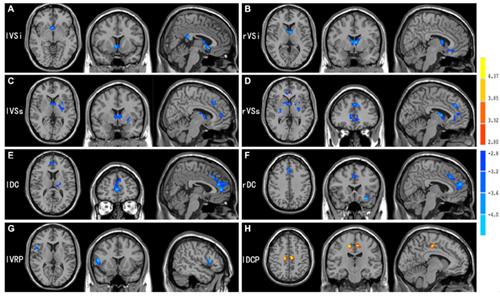

该研究运用功能连接方法对青少年网瘾患者静息态脑功能磁共振图像进行了分析,发现患者皮层-纹状体神经环路存在功能连接异常,且异常程度与患者的网瘾程度和焦虑行为等显著相关。对比文献结果发现,青少年网瘾患者该环路的功能连接异常模式与鸦片等物质成瘾有类似之处。皮层-纹状体神经环路主要负责自主运动的控制、整合调节细致的意识活动和运动反应等功能,同时还与奖赏、情感、执行和控制等高级认知功能有关。该系列研究说明网络成瘾不仅影响青少年大脑结构发育,同时还影响脑功能连接。这不仅加深了对网络成瘾神经机制的理解,而且为发展科学有效的青少年网瘾的干预手段和治疗方法提供了依据。

网瘾患者皮层-纹状体神经环路异常模式